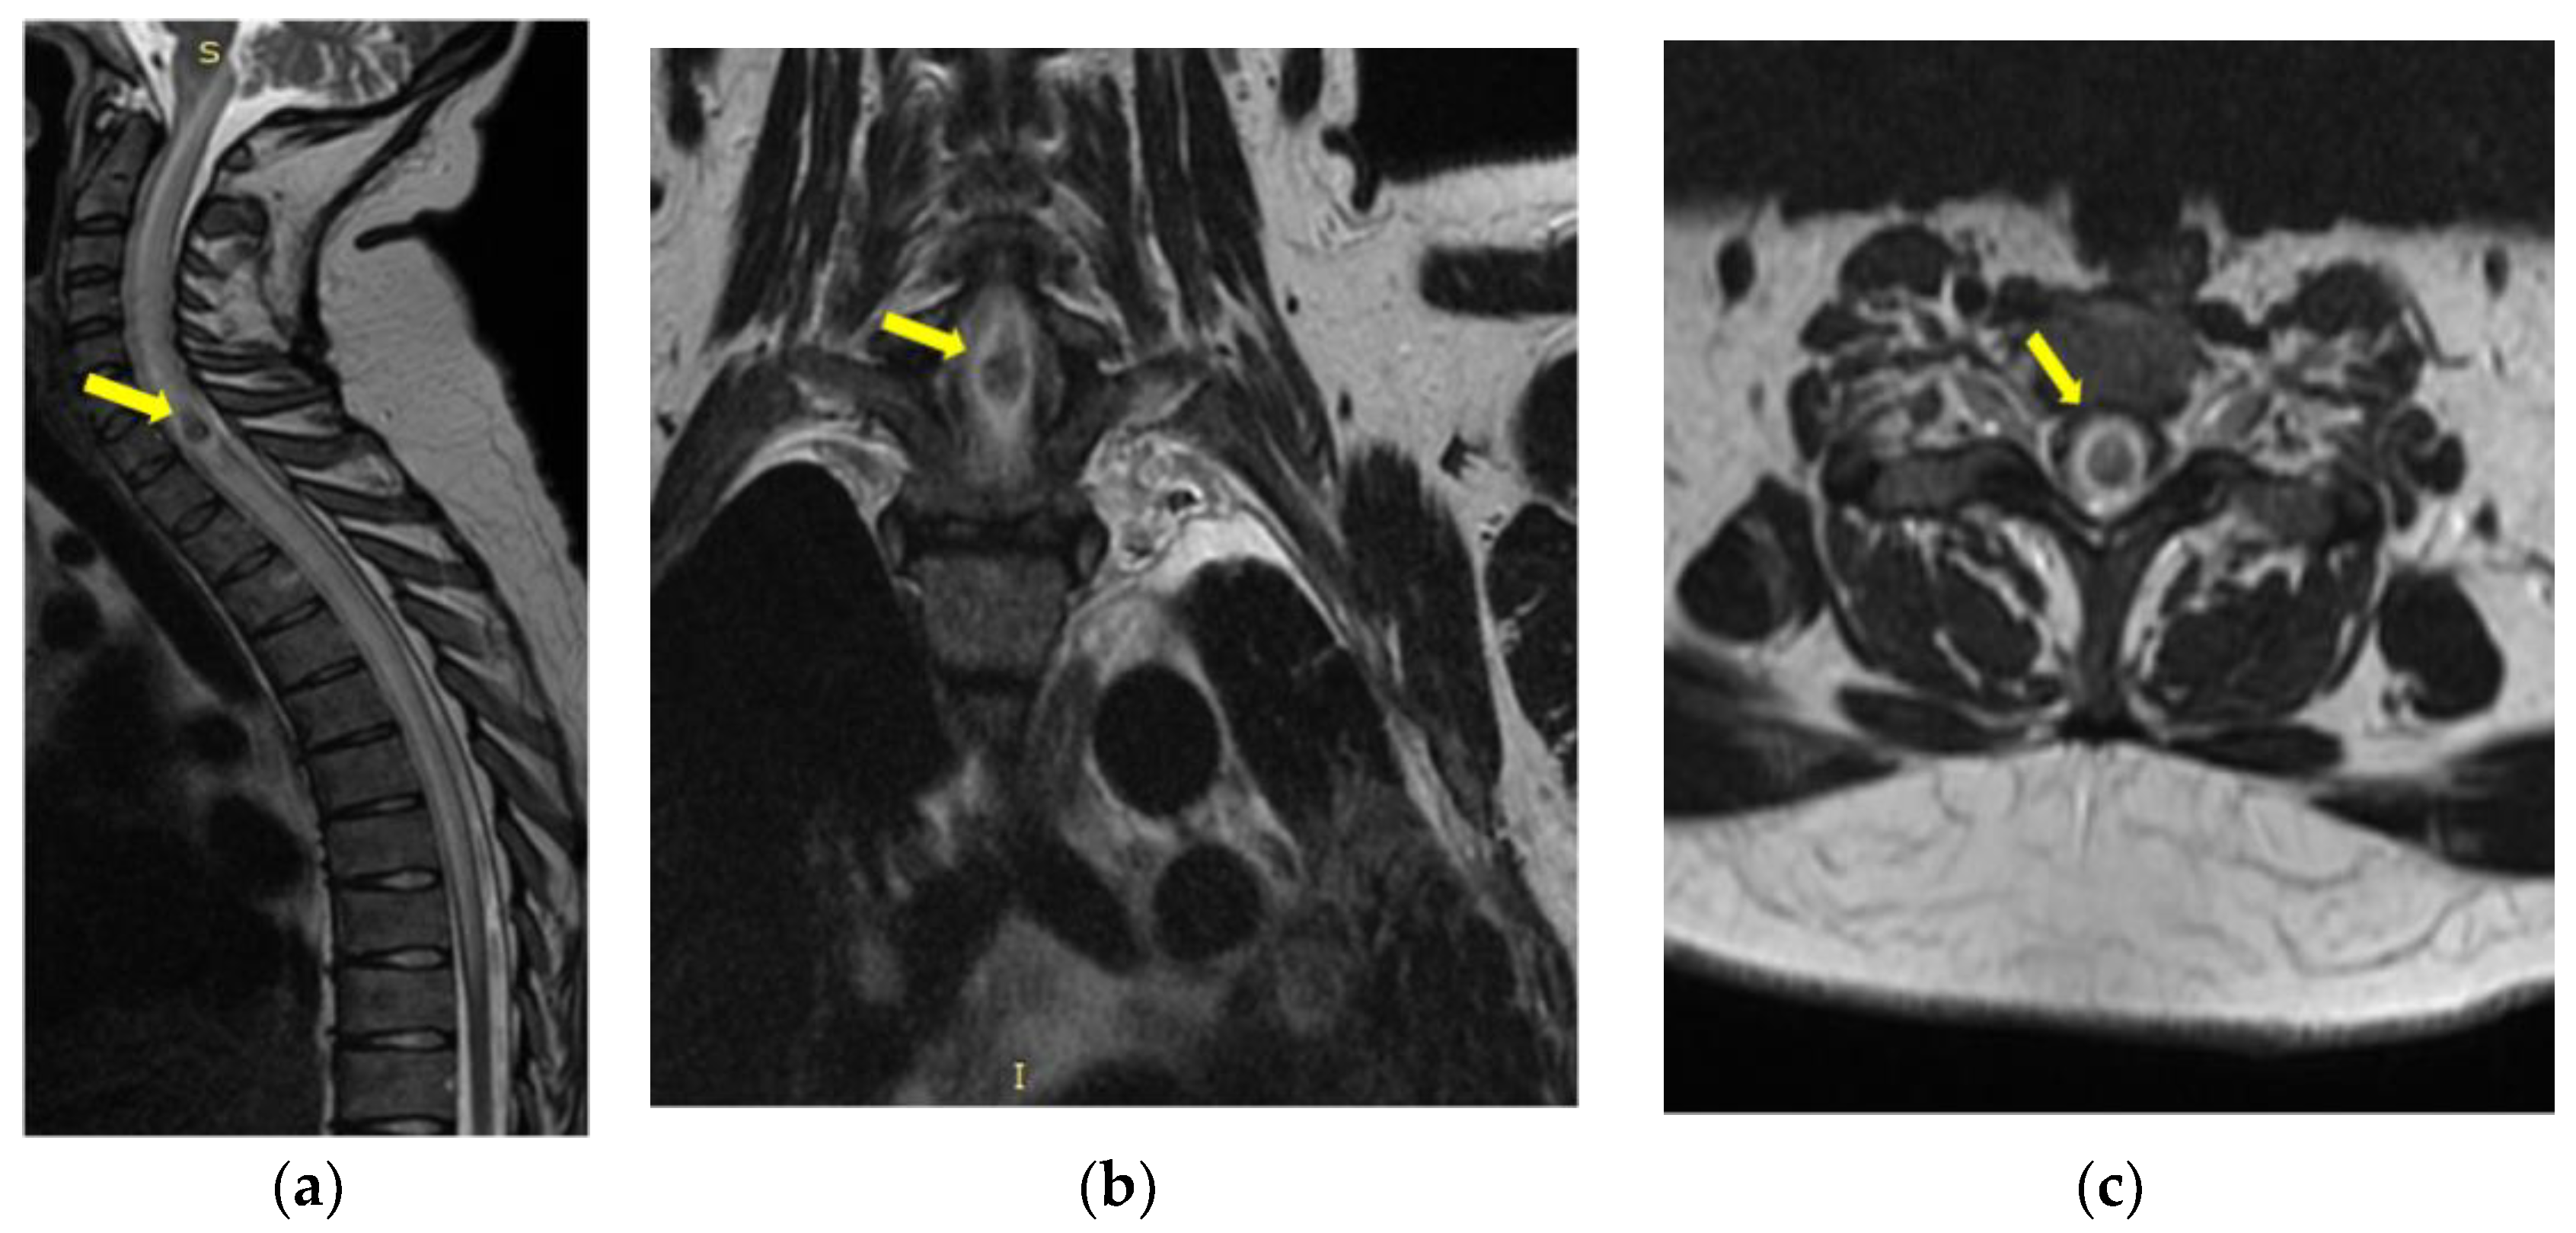

2. Detailed Case Description

- Mycological demonstration of Aspergillus fumigates hyphae by microscopy from spu-tum, microscopy and culture from bronchial aspirate, and histopathological evi-dence of the presence of Aspergillus fumigates hyphae with dichotomous branching in the spinal cord biopsy;